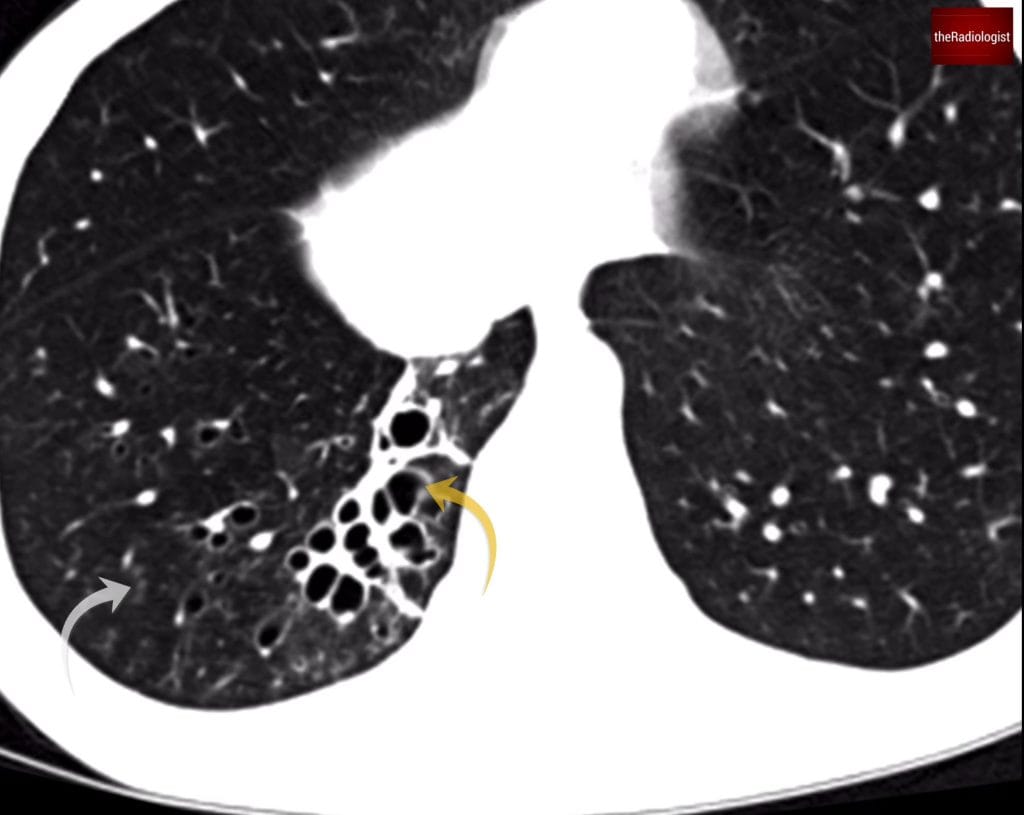

On the CT scan if we assess the right lower lobe we will see dilatation of the airways and bronchiectasis.

We can also see signs of airway inflammation:

- Bronchial wall thickening – A sign of ongoing airway inflammation.

- Groundglass centrilobular nodules – These suggest inflammation affecting the small airways, possibly infection in the context of bronchiectasis.

Within the posterior segment of the right lower lobe there is clear bronchiectasis (yellow arrow) and signs of airway inflammation. The grey arrow points at centrilobular ground nodules, a sign of small airway inflammation.

The most severe form, where airways look like clusters of cysts, sometimes described as a ‘bunch of grapes’ and this is what we can see in our case. Cystic bronchiectasis can mimic cystic lung disease or honeycombing as seen in lung fibrosis.

How can we tell the difference? with cystic bronchiectasis the cysts will follow the course of the airways and you should be able to trace the cysts back to the proximal airway.

Cystic bronchiectasis is thought to resemble a ‘bunch of grapes’.